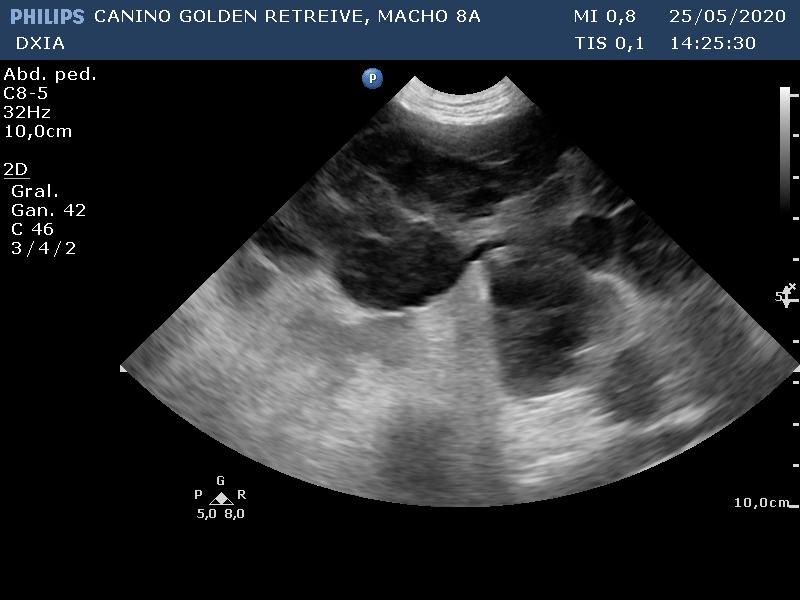

En el ecocardio, gráficamente no hay alteraciones. En la ecografía abdominal, hay gran distensión por presencia de líquido libre abdominal y alteración de todo el parenquima hepático (patrón modular marcado) con hepatomegalia.

SCOTT_CANINO GOLDEN RETREIVE-desenlace01

SCOTT_CANINO GOLDEN RETREIVE-desenlace02

SCOTT_CANINO GOLDEN RETREIVE-desenlace03